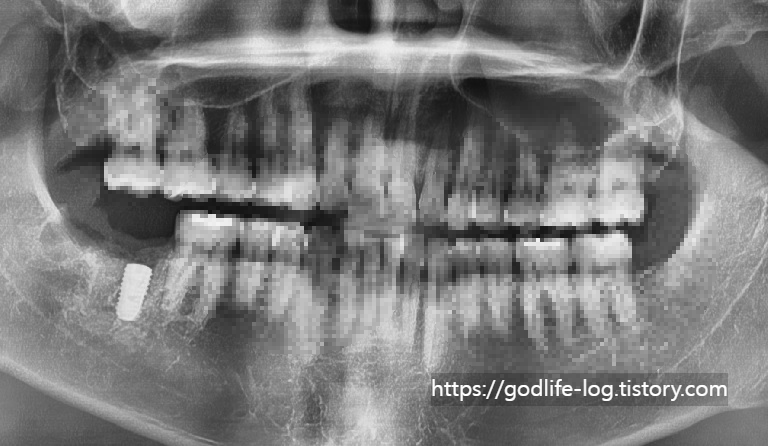

위 사진처럼 오른쪽, 왼쪽, 위, 아래 사랑니 4개 모두 일반적인 어금니와 같은 모습으로 똑바로 맹출 되어있는 경우엔 관리만 잘 된다면 크게 주변치아에 문제를 일으키지는 않습니다.

위 사진과 같이 주로 아래쪽에 있는 사랑니는 수평으로 매복되어 있는 경우가 많습니다. x-ray사진상으로는 치아가 잘 보이지만 실제 구강 내에서는 사랑니의 일부분만 보입니다. 맨 끝에 있는 어금니와 사랑니 사이에 음식물이 끼면 음식물이 잘 안 빠지고 그것 때문에 잇몸에 염증이 생기면서 잇몸이 붓고 피가 나고 정말 심한 경우에는 입을벌리기 힘든경우까지 생길 수 있습니다. 또 이런게 반복되면서 사랑니가 아닌 제2대구치라고 불리는 어금니에 영향을 주게됩니다. 위 사진과같이 충치가 심하게 생길수도있고 염증이 생기면서 사랑니와 어금니 사이에 있는 잇몸뼈를 소실되게 할수도 있습니다.이렇게 문제가 생기는 경우엔 사랑니를 발치가 필요합니다. 사랑니때문에 한번 염증이 생기면 계속 염증이 생기고, 앞치아에 안좋은 영향을 줄 수 있습니다.

위 사진은 충치가 있어서 사랑니 발치 후 신경치료를 하고 치아를 씌워서 살린 경우이지만 충치가 너무 심한경우에는 어금니까지 발치를 할 수도 있습니다.